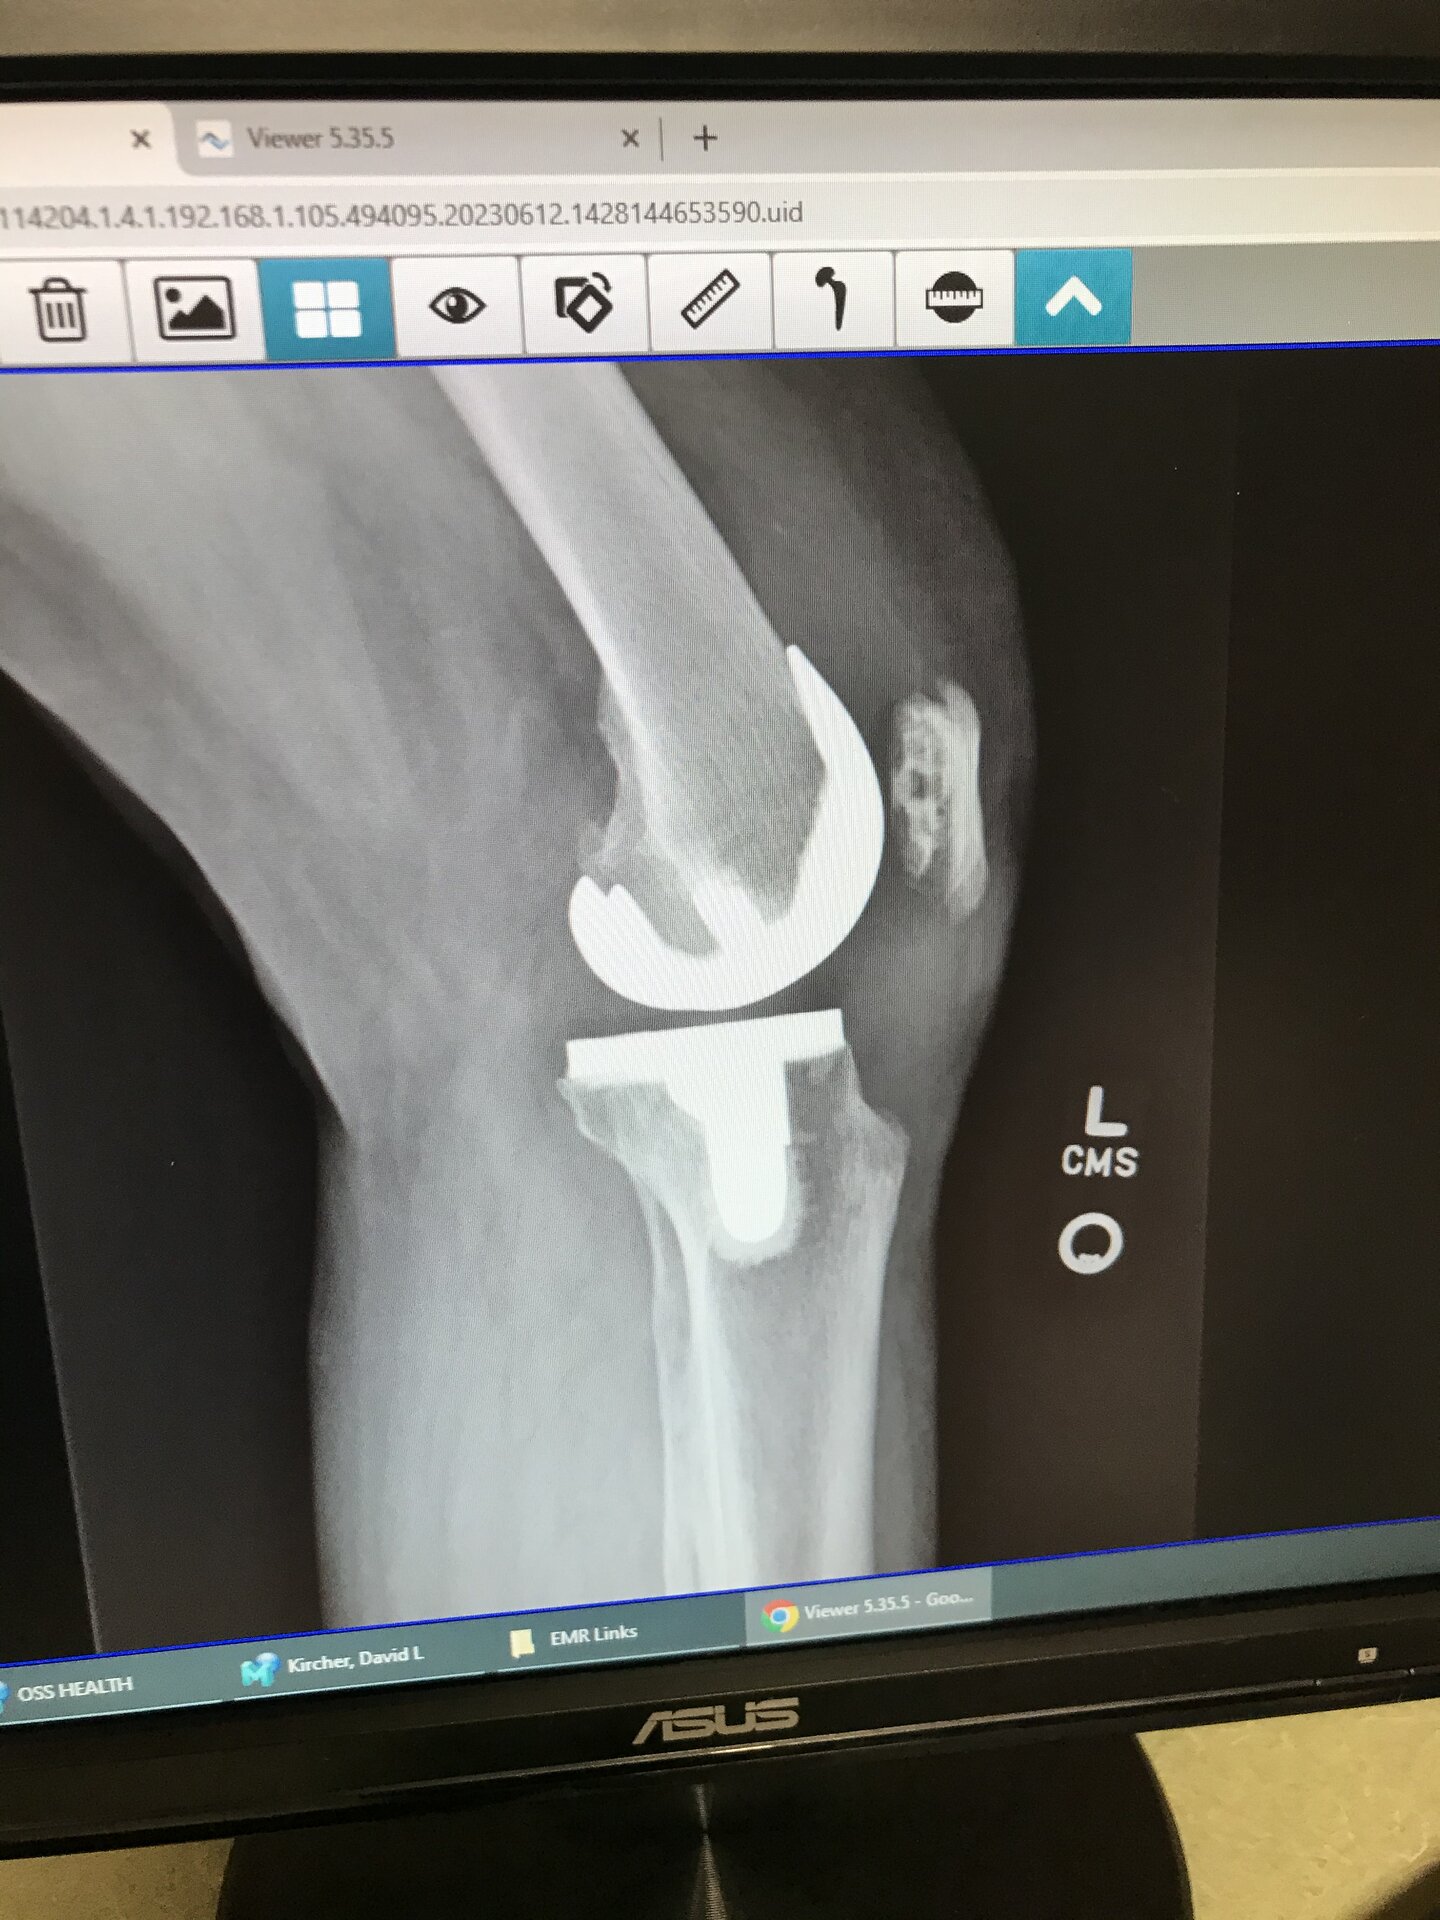

X-Rays of my knees. The one on the right is my left knee. It was done 2 years ago next month. The one on the left is my right knee that was replaced 18-20 years ago. I’d have to look it up to be sure but it’s been a long time ago. If you look and the bones and the implants you can see the difference. 5F8BE522-AB93-4666-BF4F-4B7486F4DF81.jpeg 95B54618-C230-4ECC-98AE-A43C746D1CE0.jpeg